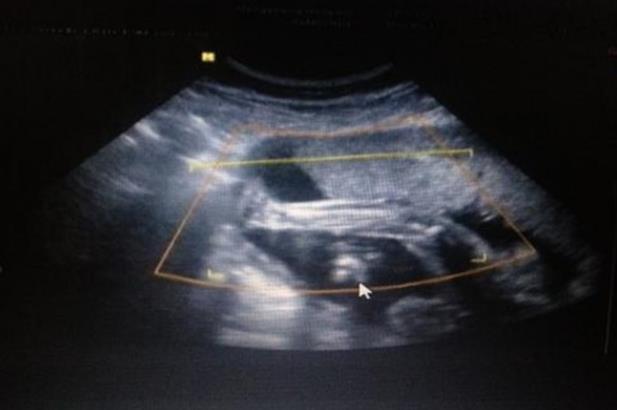

安徽中山醫(yī)院引進(jìn)了國際領(lǐng)先的輔助生殖技術(shù)和設(shè)備,使得其在人工授精、體外受精-胚胎移植、卵胞刺激治療等方面擁有強(qiáng)大的技術(shù)支持。同時(shí)該院還擁有一支專業(yè)化、高素質(zhì)的輔助生殖專家團(tuán)隊(duì),確保治療方案更加科學(xué)、個(gè)性化。

作為一所三甲綜合性醫(yī)院,安徽中山醫(yī)院擁有先進(jìn)設(shè)備和高水平的專業(yè)團(tuán)隊(duì),為試管嬰兒技術(shù)提供了優(yōu)越的設(shè)備條件。胚胎培養(yǎng)箱、激光操作系統(tǒng)等高端設(shè)備,讓安徽中山醫(yī)院在試管嬰兒技術(shù)上更加獨(dú)具優(yōu)勢(shì)。

安徽中山醫(yī)院輔助生殖專科自2004年開展以來,已經(jīng)累計(jì)為數(shù)萬對(duì)不孕不育夫婦解決了問題,并積累了豐富的臨床經(jīng)驗(yàn)。這些經(jīng)驗(yàn)使得其在治療方案制定、手術(shù)操作等方面都顯得更加得心應(yīng)手。